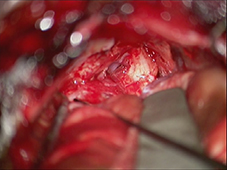

< 手術所見 >

腫瘍消失、顔面神経麻痺なし

ナビゲーションシステムの使用